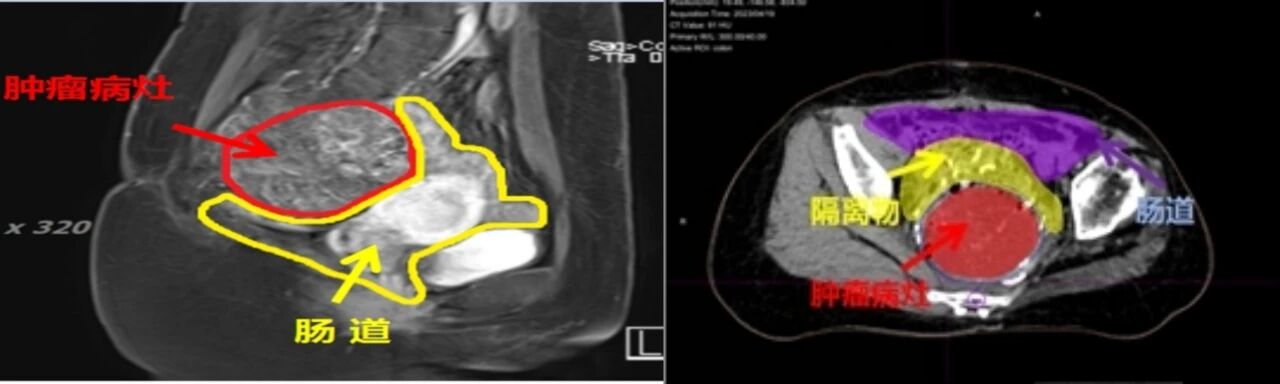

甘肃省武威肿瘤骨与软组织肿瘤多学科MDT诊疗团队,设计一种新的重离子术中放疗新方法,脏器与癌肿间外科置入Spacer隔离物重离子治疗技术,能够解决解决以下问题:

7、生活质量的问题;因碳离子治疗采用大分割短疗程,当肿瘤与胃肠道位置比较接近时, 因胃肠不能耐受高剂量放疗,所以考 虑到胃肠道的放疗耐受量,距离胃肠道近的部分肿瘤在 治疗时不能接受根治性剂量。在碳离子治疗前,进行开腹或腹腔镜手术,把纱布垫放置在肿瘤与相邻胃肠道之间,拉开两者之间的距离, 后进行定位及计划设计,保证胃肠道无放疗受量,从未 给与肿瘤根治性剂量。

在已经经过治疗的73例脊索瘤当中,共计完成9例此项技术,获得了很好的肿瘤控制效果;患者的骶丛神经功能获得了良好的保留,具有自主的大小便控制功能;治疗并发症明显减少,手术和放疗的相关并发症发生率明显减少;患者的可接受程度明显增加。在随访的过程中获得患者的好评。